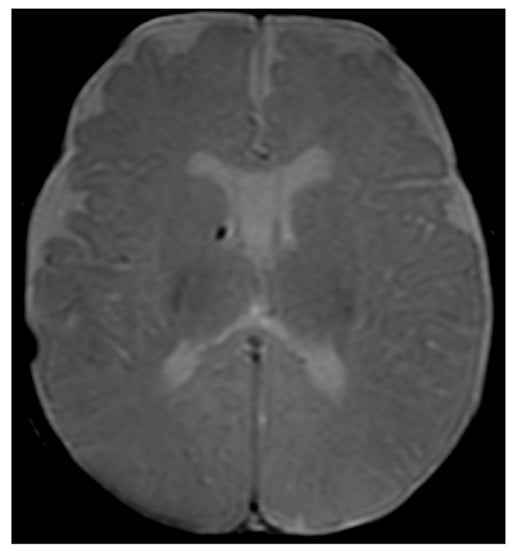

Considering the persistence of pathological signs on cuS, a brain MRI was performed at two months and three weeks of corrected age (CA), showing a hypointense nodular alteration through gradient echo weighted images (Figure 1).

Figure 1. Brain MRI with axial T2-gradient echo image at 2 months and 3 weeks of life. Punctate susceptibility focus, suspicious for calcification/hemosiderin, in the right germinal matrix is visible.